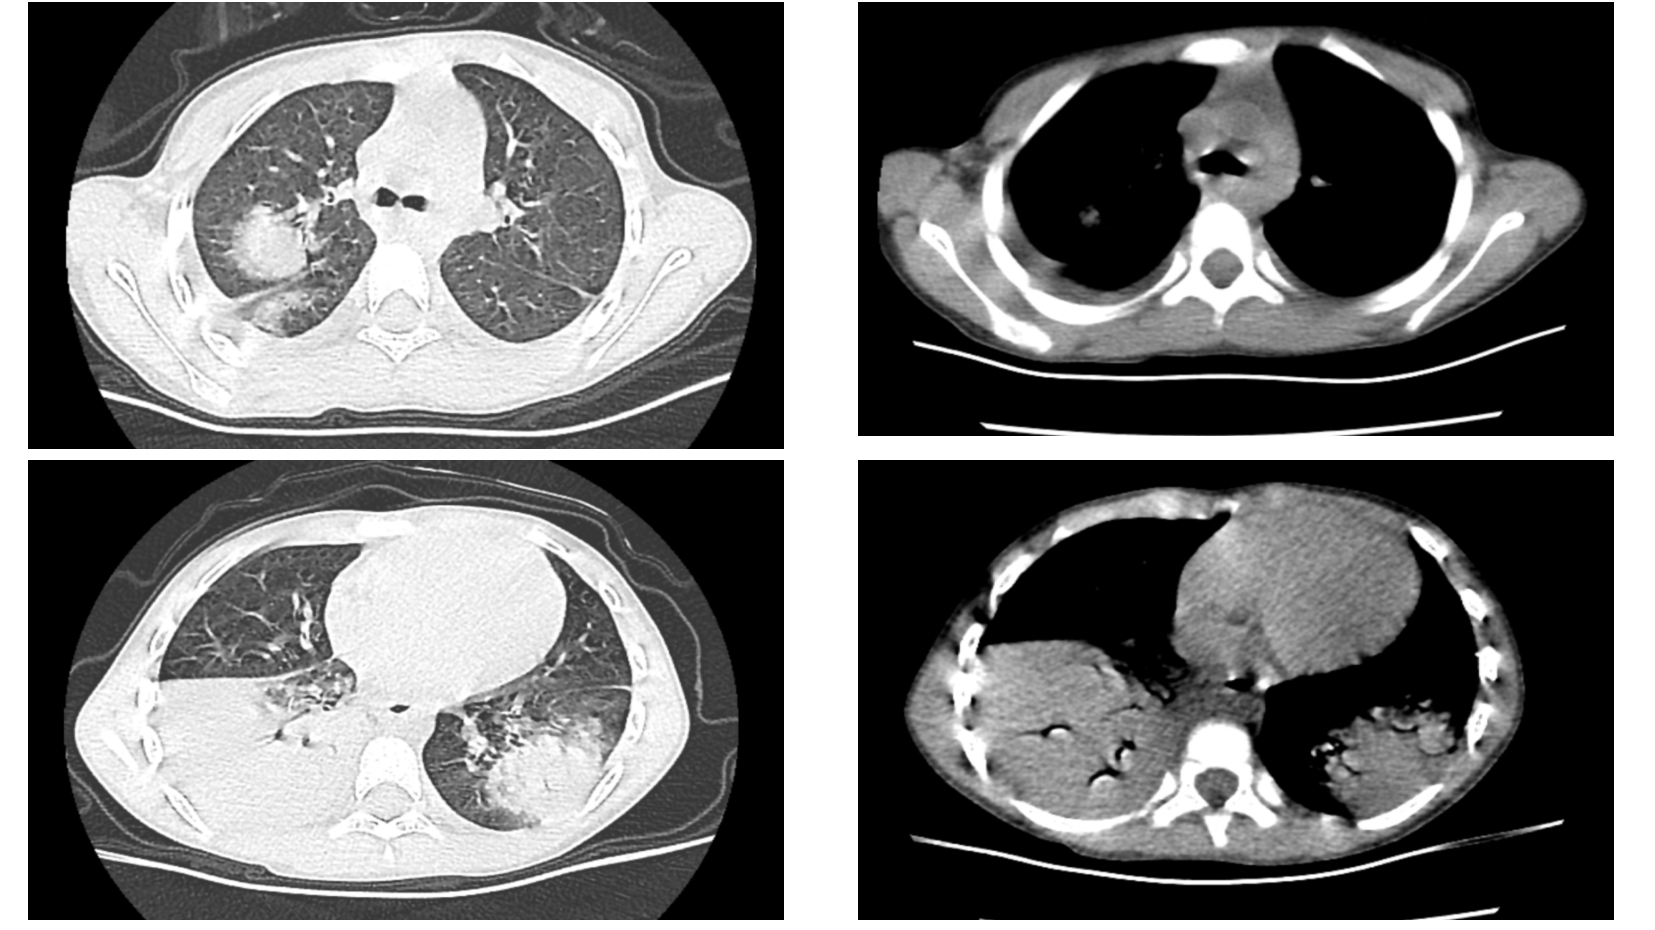

越过“肺炎”的陷阱:探秘一例儿童肺栓塞的元凶